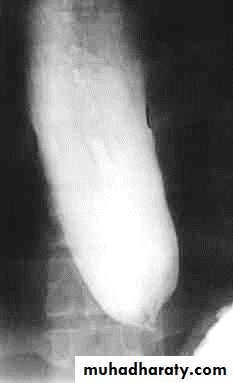

PULSION DIVERTICULUM

Due to:raised intra-luminal tension

Chocking after meal .

In cervical portion at level of C5

Posteriorly (Killience dehiscent)

Lateral view show increased pre-vertebral space with air fluid level.

Confirmed by Ba. Swallow.

TRACTION DIVERTICULUM

Out pouching of lumen laterally due to fibrosis & adhesions ( post-Tb.)

In the middle third at level of hilum

Up ward direction of diverticulum

Irregular base

On the far left a traction diverticulum (arrow) due to hilar granulomatous disease. Calcified adenopathy (asterisk).

In the middle a pulsion diverticulum (arrow) due to high intra luminal pressure.

On the right multiple pulsion diverticula (arrows)

CONGENITAL DIVERTICULUM

Asymtomatic unless complicated.

At lower part of esophagus above the diaphragm (Epi-phrenic)

Lateral or posterior in position.